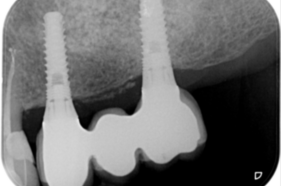

Zubní implantát je šroubovitý podpůrný pilíř, který nahrazuje přirozený kořen zubu. Implantát je zaveden do čelisti, kde se nechá zhojit s kostí, po tuto dobu se většinou nezatěžuje. Implantát je vyroben z čistého technického titanu nebo ze slitiny titanu a zirkonia, je lidským organismem přijímán bez komplikací, alergické reakce se nevyskytují.

Zubní implantát se zavádí chirurgicky v lokálním znecitlivění.